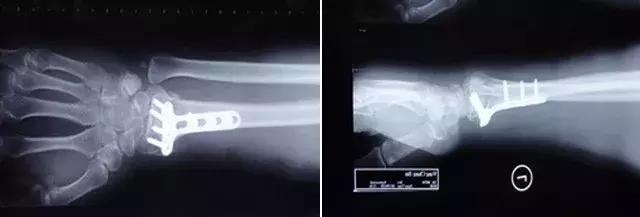

张大爷的骨折就属于不稳定的桡骨远端粉碎性骨折,早期虽然复位很好,但是随着患区组织肿胀的减轻,石膏就会出现松动,那么因为骨折端不稳定,复位可能就会出现不同程度的丢失,如果在不可接受范围,而这个时候可能已经错过了手法复位的理想时期,就基本需要手术复位了。

还说张大爷,他的骨折属于不稳定骨折,虽然跑位了,但却是容易愈合的部位,如果不再干预,骨折也仍然会愈合,但因为骨折端会短缩成角,属于畸形愈合,这就会影响以后的关节功能。

听完陈炜医生全面专业的解释,张大爷心里的疙瘩完全解开了。“原来我骨头又跑位了主要还是因为我这属于不稳定的骨折,我完全听从您的建议,愿意接受手术治疗”。